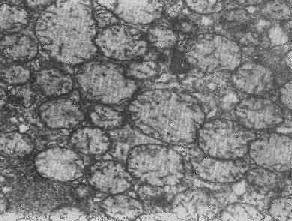

2.大小改变 细胞损伤时最常见的改变为线粒体肿大。根据线粒体的受累部位可分为基质型肿胀和嵴型肿胀二种类型,而以前者为常见。基质型肿胀时线粒体变大变圆,基质变浅、嵴变短变少甚至消失(图1-9)。在极度肿胀时,线粒体可转化为小空泡状结构(图1-10,图1-11)。此型肿胀为细胞水肿的部分改变。光学显微镜下所谓的浊肿细胞中所见的细颗粒即肿大的线粒体。嵴型肿较少见,此时的肿胀局限于嵴内隙,使扁平的嵴变成烧瓶状乃至空泡状,而基质则更显得致密。嵴型肿胀一般为可复性,但当膜的损伤加重时,可经过混合型而过渡为基质型。

图1-9 线粒体肿